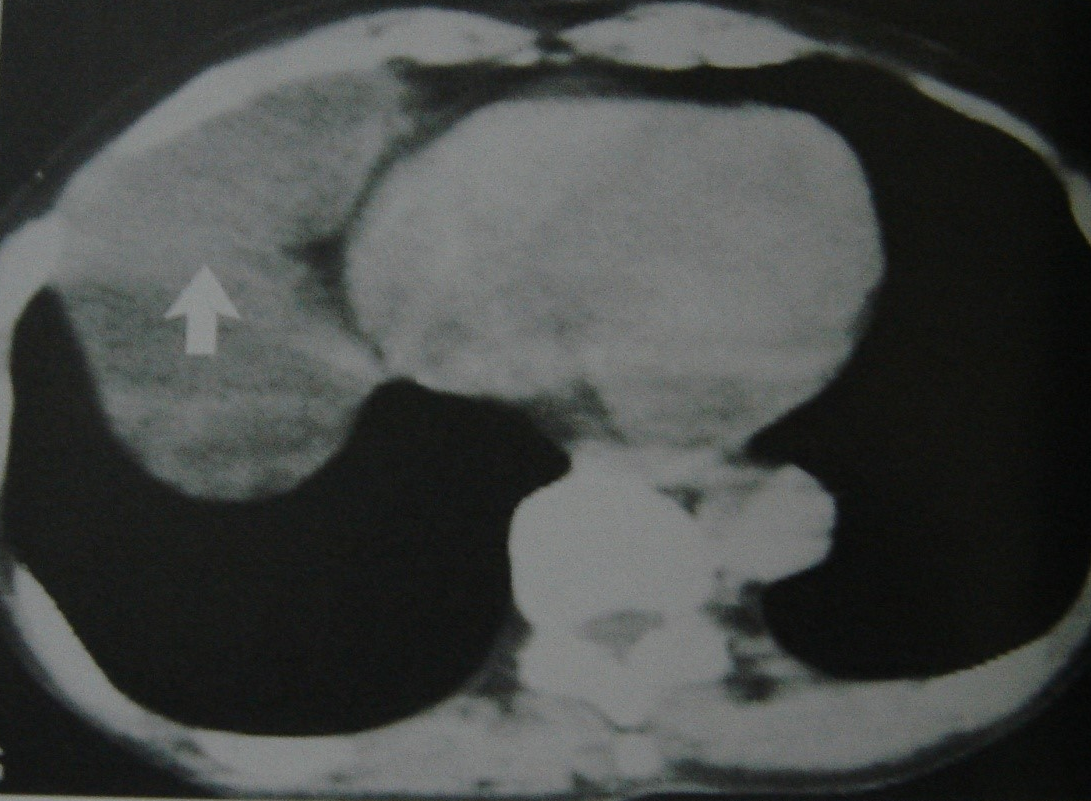

Kəskin mediastinitin diaqnozunu dəqiqləşdimək üçün ən vacib müayinə KT-dir. KT-də divararalığında ödem, maye, hava, kontrast ekstravazasiyası mediastinitin xarakterik əlamətləridir.

- KT-də divararalığında ödem, maye, hava, bəzən də kontrast ekstravazasiyası (Şəkil 10)

Şəkil 10. KT. Kontrastın qida borusundan ekstravazasiyası